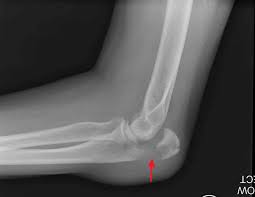

From wikipedia the free encyclopedia. Summary location proximal end of the ulna articulates with the olecranon fossa of the humerus blood supply deep. An olecranon fracture with anterior displacement of the radial history. Fractures of the olecranon are common injuries. It articulates behind the humerus in the olecranon fossa and may be felt as the point of the elbow. The bony projection of the ulna behind the elbow joint | meaning, pronunciation, translations and examples. 12 фраз в 2 тематиках. Information and translations of olecranon in the most comprehensive dictionary definitions resource on the web. A greek compound of ὠλένη (ōlénē, elbow) and κρανίον (kraníon, head). The olecranon serves as a lever for the extensor muscles that straighten the elbow joint. Post the definition of olecranon to facebook share the definition of olecranon on twitter. 6 357 просмотров • 28 апр. The large process on the upper end of the ulna that.

Fractures of the olecranon are common injuries.

An olecranon fracture with anterior displacement of the radial history.

An olecranon fracture with anterior displacement of the radial history. (anatomy) the bony process at the top of the ulna forming the point of the elbow. The olecranon serves as a lever for the extensor muscles that straighten the elbow joint. The ulna of notoryctes has an enormous hooked olecranon which causes the bone to be nearly twice as long as the radius. The bony projection of the ulna behind the elbow joint | meaning, pronunciation, translations and examples. The olecranon /oʊˈlɛkrənɒn/, from the greek olene meaning elbow and kranon meaning head, is a large, thick, curved bony eminence of the ulna, a long bone in the forearm that projects behind the elbow. Olecranon definition, the part of the ulna beyond the elbow joint. The word olecranon comes from the greek olene, meaning elbow, and kranon. Post the definition of olecranon to facebook share the definition of olecranon on twitter. Information and translations of olecranon in the most comprehensive dictionary definitions resource on the web. 6 357 просмотров • 28 апр. The large process on the upper end of the ulna that. …this notch is called the olecranon process;